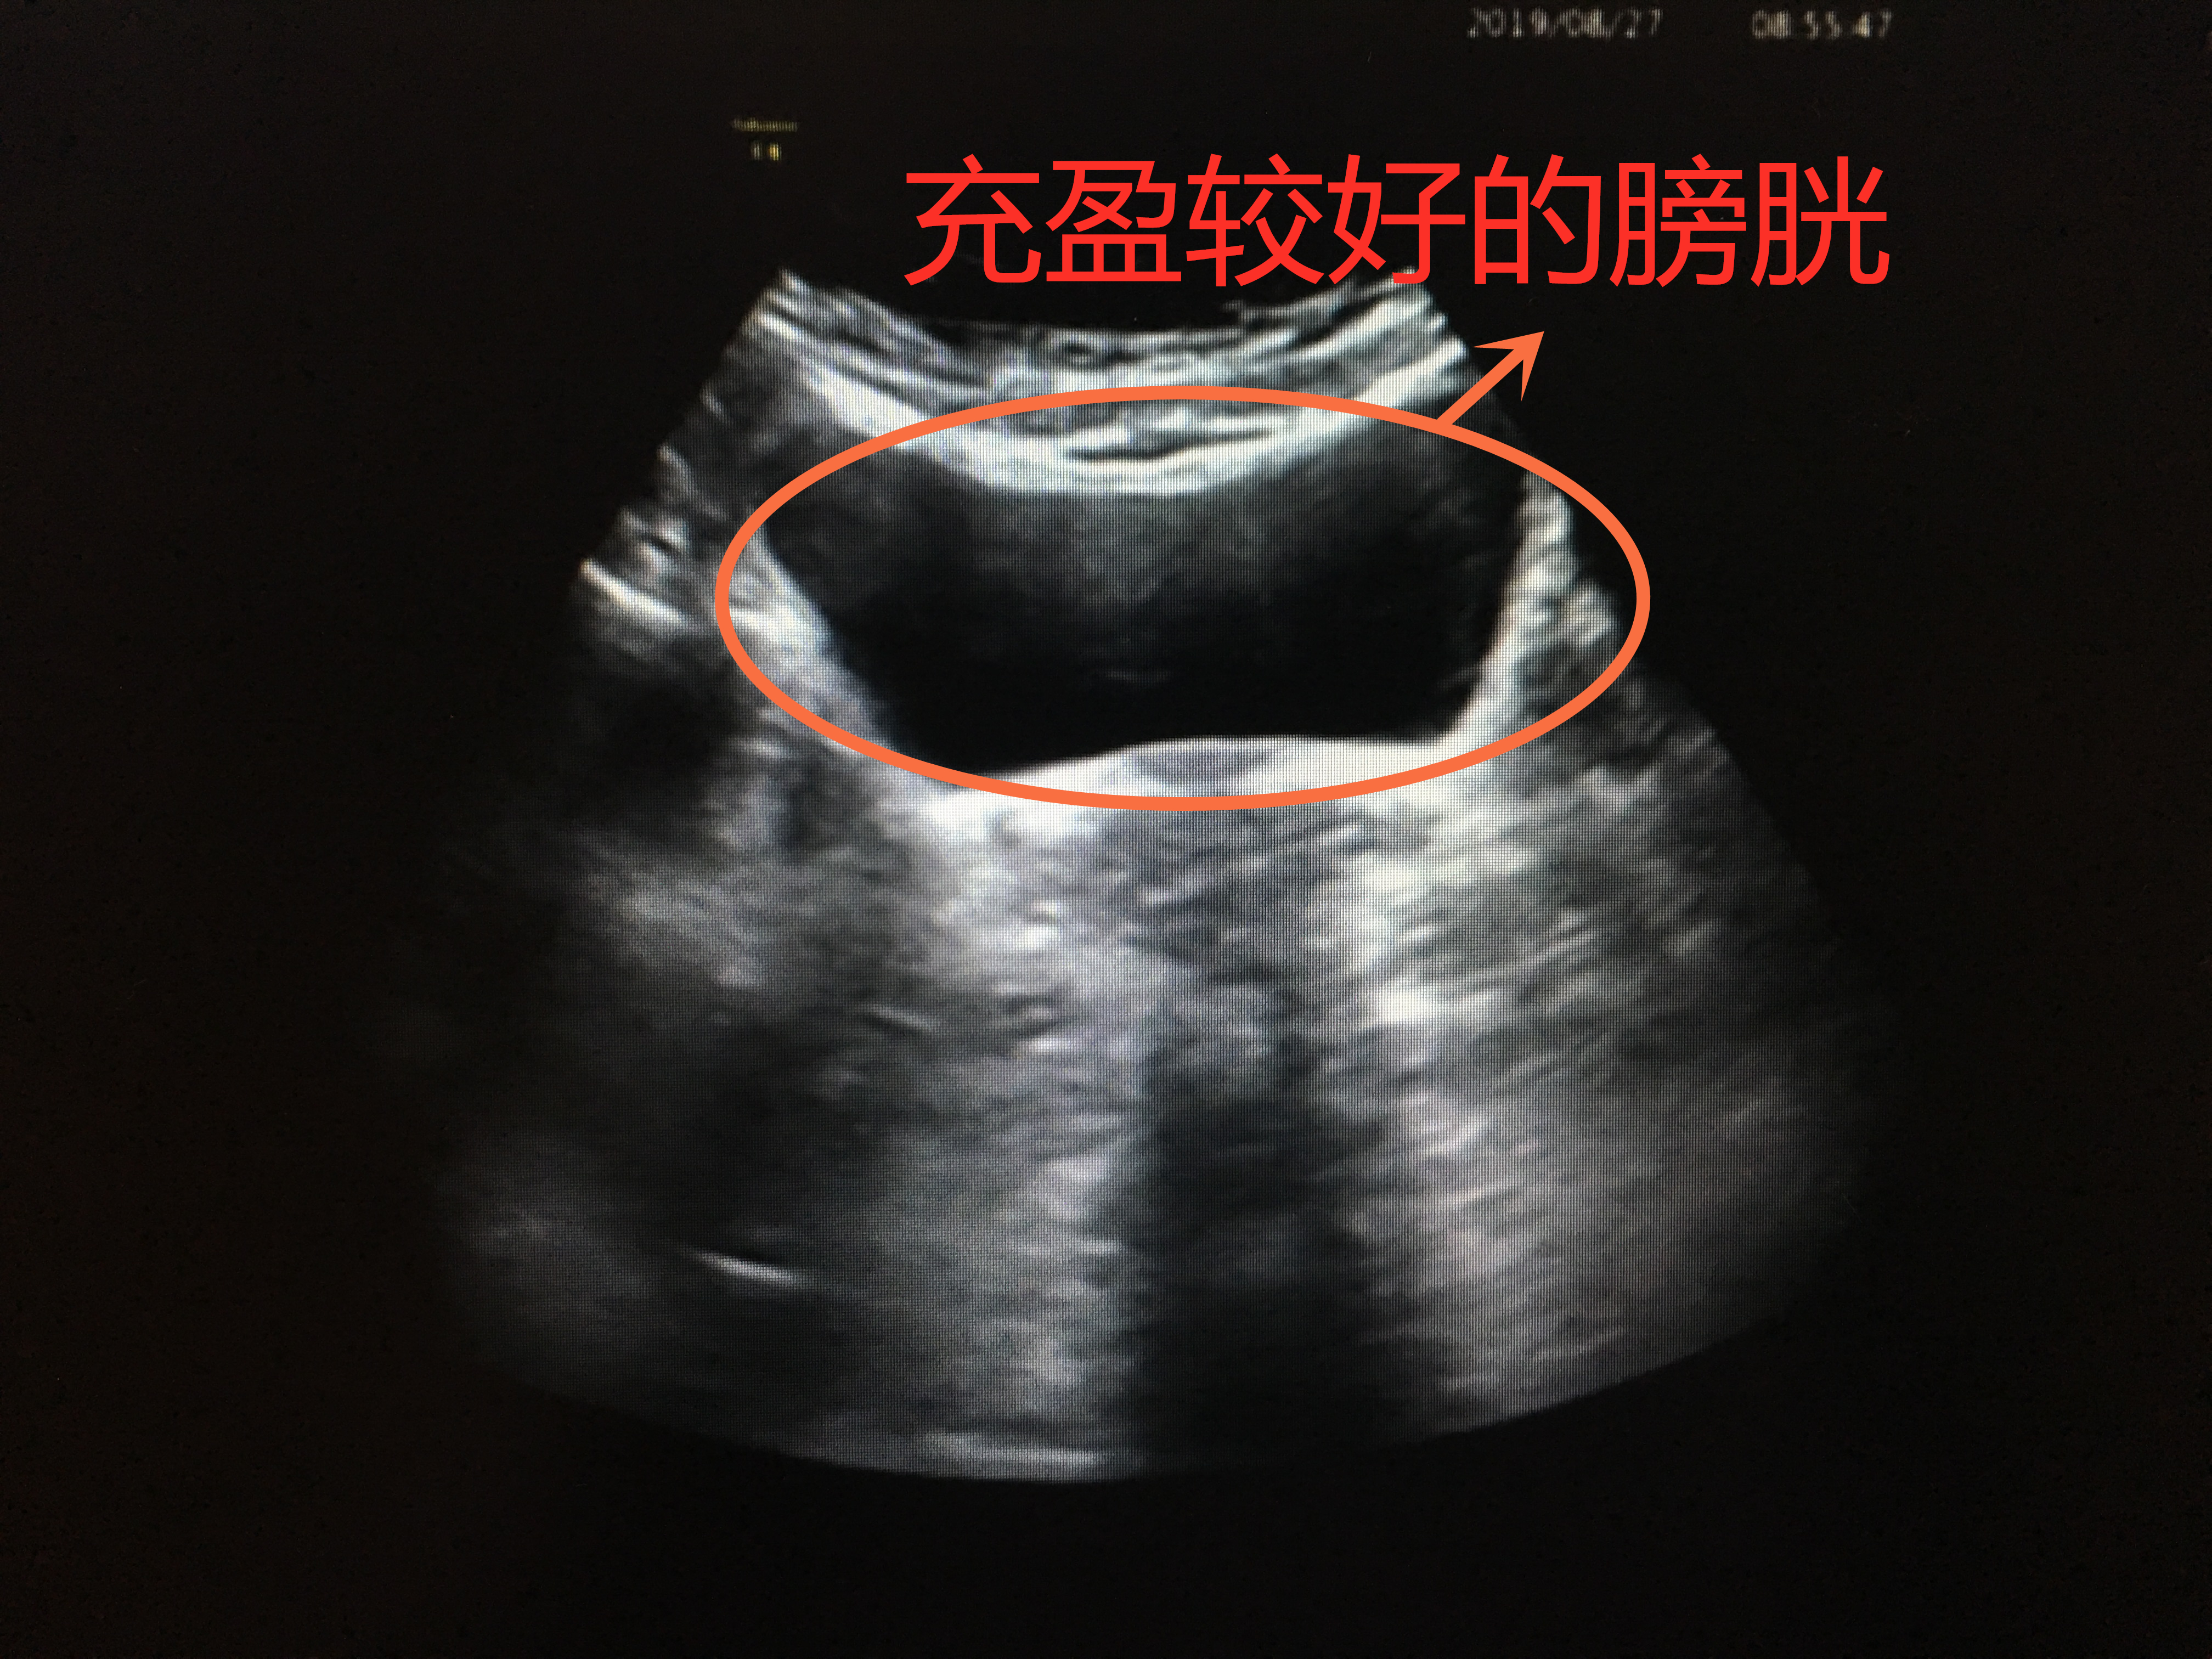

膀胱B超:让你憋尿就努力憋住吧

下腹痛、小便痛或者尿频尿急等情况的时候,医生一般会建议做一个泌尿系彩超检查,其中就包括了膀胱B超检查,这是后就有一件必须完成的事:憋足够的尿。

憋尿较好,膀胱充盈

憋尿欠佳,膀胱欠充盈

膀胱就像一个皮球,当你往里面打足气时,皮球便充分撑开;而当打的气不够时,皮球就瘪着。所以,当你憋尿充足时,膀胱充盈起来,把每个角落都撑开,检查时便一览无遗;当憋尿不够,充盈欠佳时,局部可能皱褶起来,隐藏病灶。所以,下次医生让你憋尿的时候,就努力的憋吧。